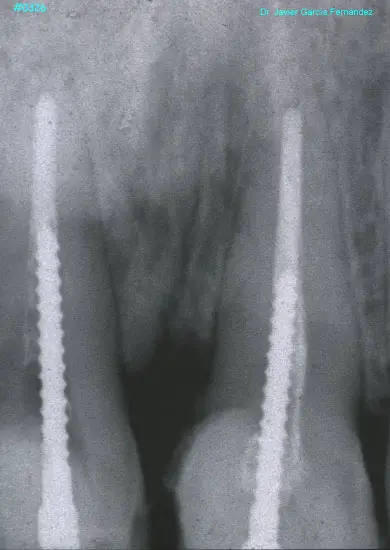

ATLAS DE CIRUGIA PERIODONTAL

image371